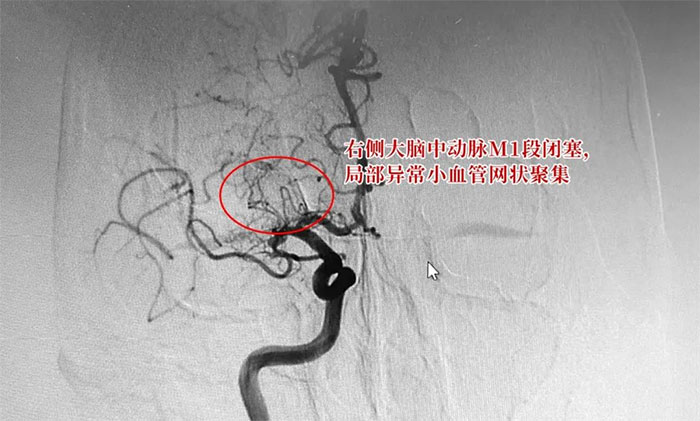

六旬男子突发言语不清,肢体活动障碍 原来是烟雾病“作祟”

烟雾病是一组以双侧颈内动脉末端和(或)大脑前动脉、大脑中动脉起始部缓慢进展性狭窄以致闭塞,出现代偿性异常血管网为特点的脑血管病。随着病情发展,可出现脑梗死、脑出血等症状,且容易持续进展和反复...【详细】